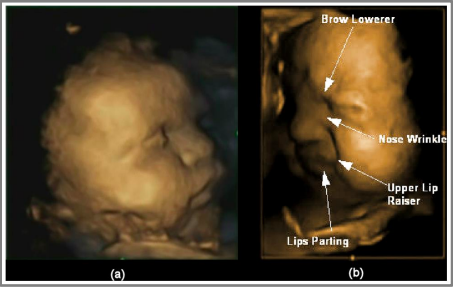

• The scientifically-measurable and observable 4D ultrasound provides a visual tool of the pain an unborn child 20 weeks post-fertilization is able to feel.

The 20 Week Protection Bill (the formal name is the Pain Capable Unborn Child Protection Act). This bill was introduced in Delaware's Senate in March 2019 and in the House (SB21 and HB52). It protects babies at 20 weeks and older from the violent act of abortion. Scientific studies prove that 20 week old babies feel the pain of abortion.